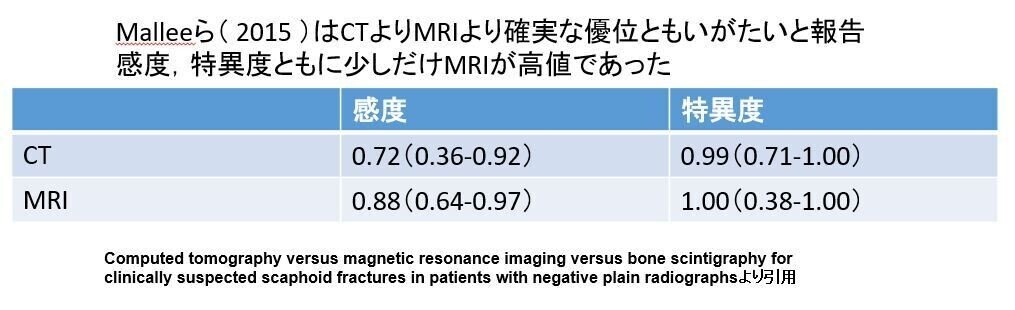

CT・MRI

実は両者は大きな差はなかったりします

でも

CTでもわかりにく

不顕性骨折や骨挫傷がわかる

MRIがゴールデンスタンダードでは?

たしかにそうなんですが

文献には大多数でどの検査よりも有用であり

ランニングコストがかかる以外は

CTの放射線被ばくと違い

人体には何のデメリットもありません

だがしかし

MRIにもこんなネガティブデータが存在します